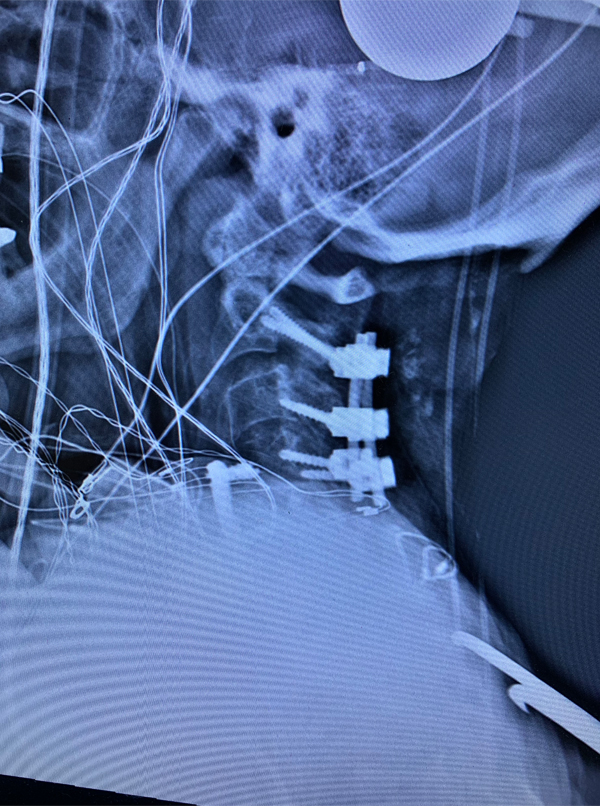

Figure 3: Postoperative lateral c-spine x-ray showing removal of prior long posterior construct with final short segment fusion C2-C4. Note addition of bilateral C2 pars screws.